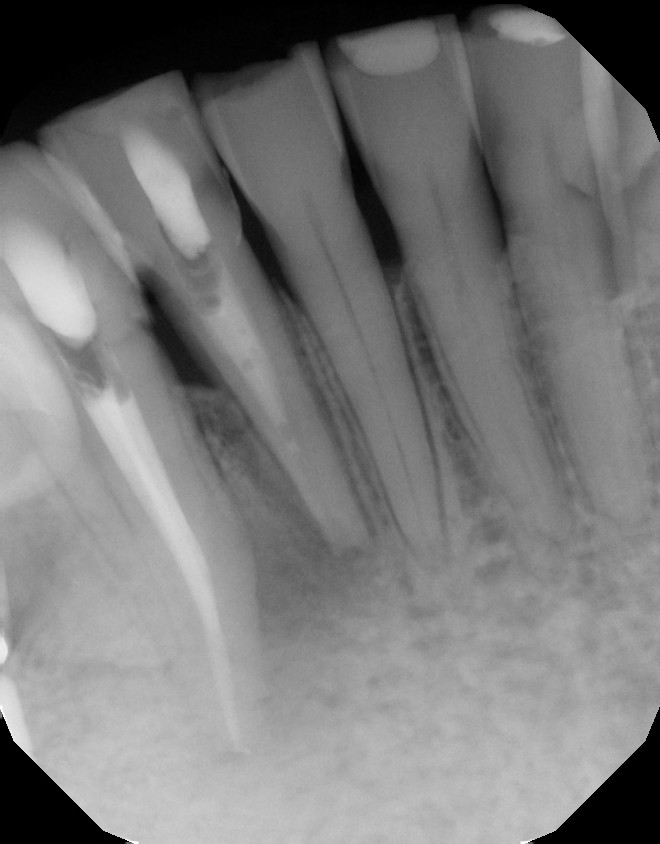

| CBCT shows the apical and lateral bone loss on #26 and #27. The lateral bone loss on #27 is also suggestive of a possible root fracture, but since the tooth is necrotic, radiographic appearance alone is not enough evidence to diagnose this with a root fracture. CBCT also shows a 2 canaled root form on #26. |

| There was concern of a possible root fracture, but none could be see internally with microscope. CaOH medicated dressing was placed after initial debridement and NaOCl irrigation. |

| After 3 months in CaOH, we opened and examined again and could find no fractures. Another application of CaOH medicated dressing was placed. |

| After 6 months of CaOH therapy we saw significant bone healing. The canals were obturated and case completed. |